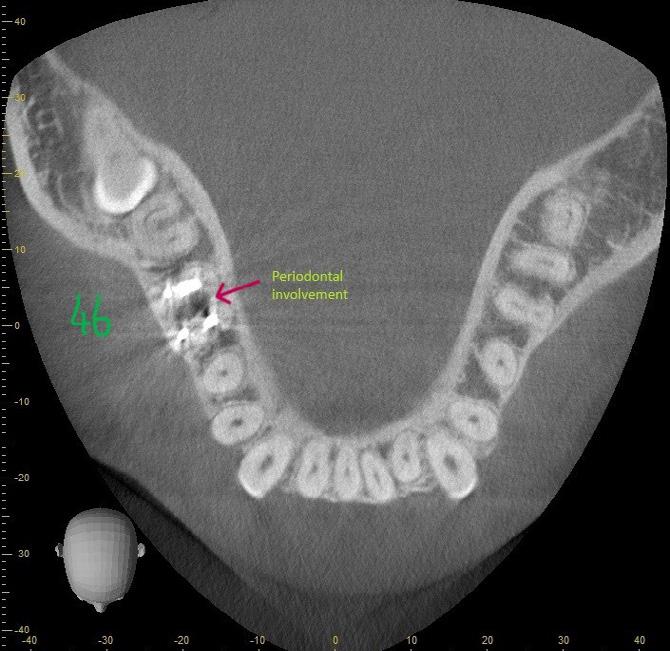

A 37-year-old female (Mrs H. K.) was referred for endodontic assessment and management of teeth 16, 26 and 46 before orthodontic space management. Clinical and radiographic evaluation, including CBCT scanning, revealed that teeth 16

and 26 were asymptomatic clinically; however, imaging confirmed the presence of missed mesiopalatal root canals, short obturation lengths in other canals, and distinct periapical radiolucencies. Both maxillary molars were diagnosed as previously root-filled with inadequate quality, exhibiting infected rootcanal systems (RCS), chronic apical periodontitis, and external apical inflammatory resorption associated with restoration breakdown, cracks, and recurrent decay. Tooth 46 shared similar diagnostic features but also demonstrated concurrent periodontal involvement, indicating a combined endodontic–periodontal lesion.

skeletal disharmony. Retaining teeth 16 and 26 was strategically important to preserve posterior anchorage, maintain vertical dimension, and support controlled space distribution during anterior alignment. Successful endodontic retreatment of these molars would provide stable posterior support, enabling more predictable arch coordination and potentially reducing treatment duration. Conversely, the extraction of 46, which had been compromised by endodontic and periodontal pathology, was expected to simplify lower-arch alignment and create efficient space for resolving anterior irregularities. Thus, the endodontic diagnosis directly informed orthodontic sequencing and biomechanics, ensuring that all tooth movement would occur within a biologically stable, infection-free environment.

Figure 1: CBCT sagittal section demonstrating periodontal bone loss involving the furcation area of tooth 46.

Figure 2: CBCT transverse section demonstrating bone loss involving the furcation area of tooth 46.